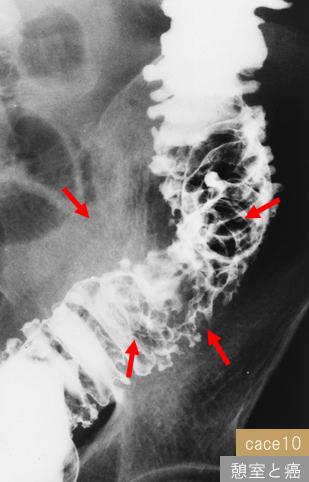

질환(병리주체)의 분류 기타/

부위(장기별) 대장/하행

검사방법 X-P

종양의 육안분류 1형(종괴형)/

종양의 최대경(밀리미터) 30~34

종양의 심달도 ss(a1)